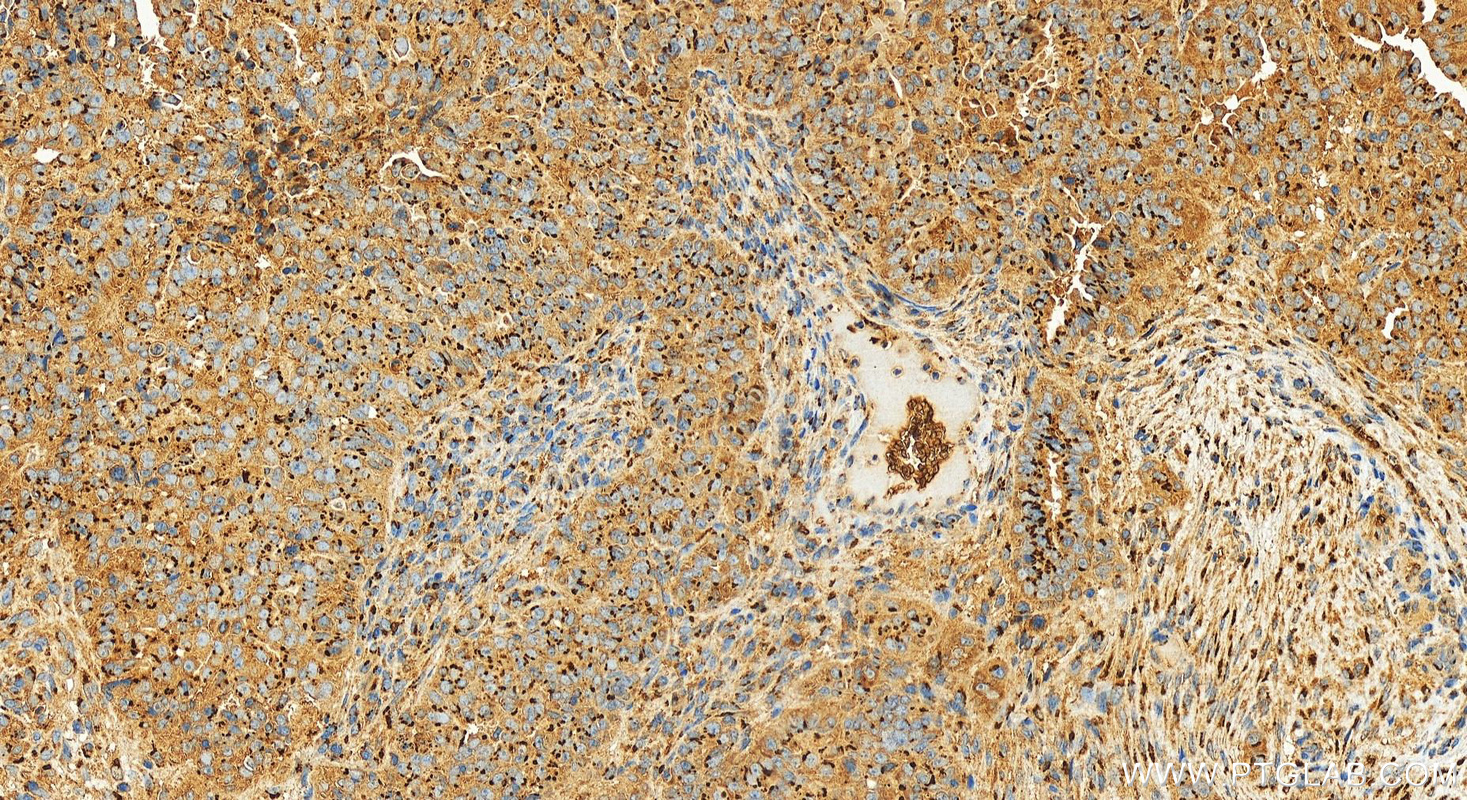

| Positive IHC detected in | human stomach cancer tissue, human liver cancer tissue, human ovarian cancer, human stomach tissue Note: suggested antigen retrieval with TE buffer pH 9.0; (*) Alternatively, antigen retrieval may be performed with citrate buffer pH 6.0 |

| Immunohistochemistry (IHC) | IHC : 1:300-1:1200 |